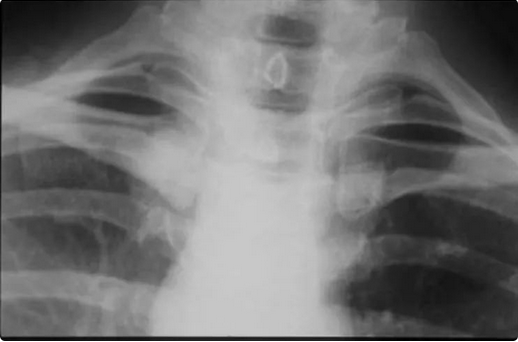

绝经后的女性患者,右胸骨出现扩大的肿块与前肿胀。